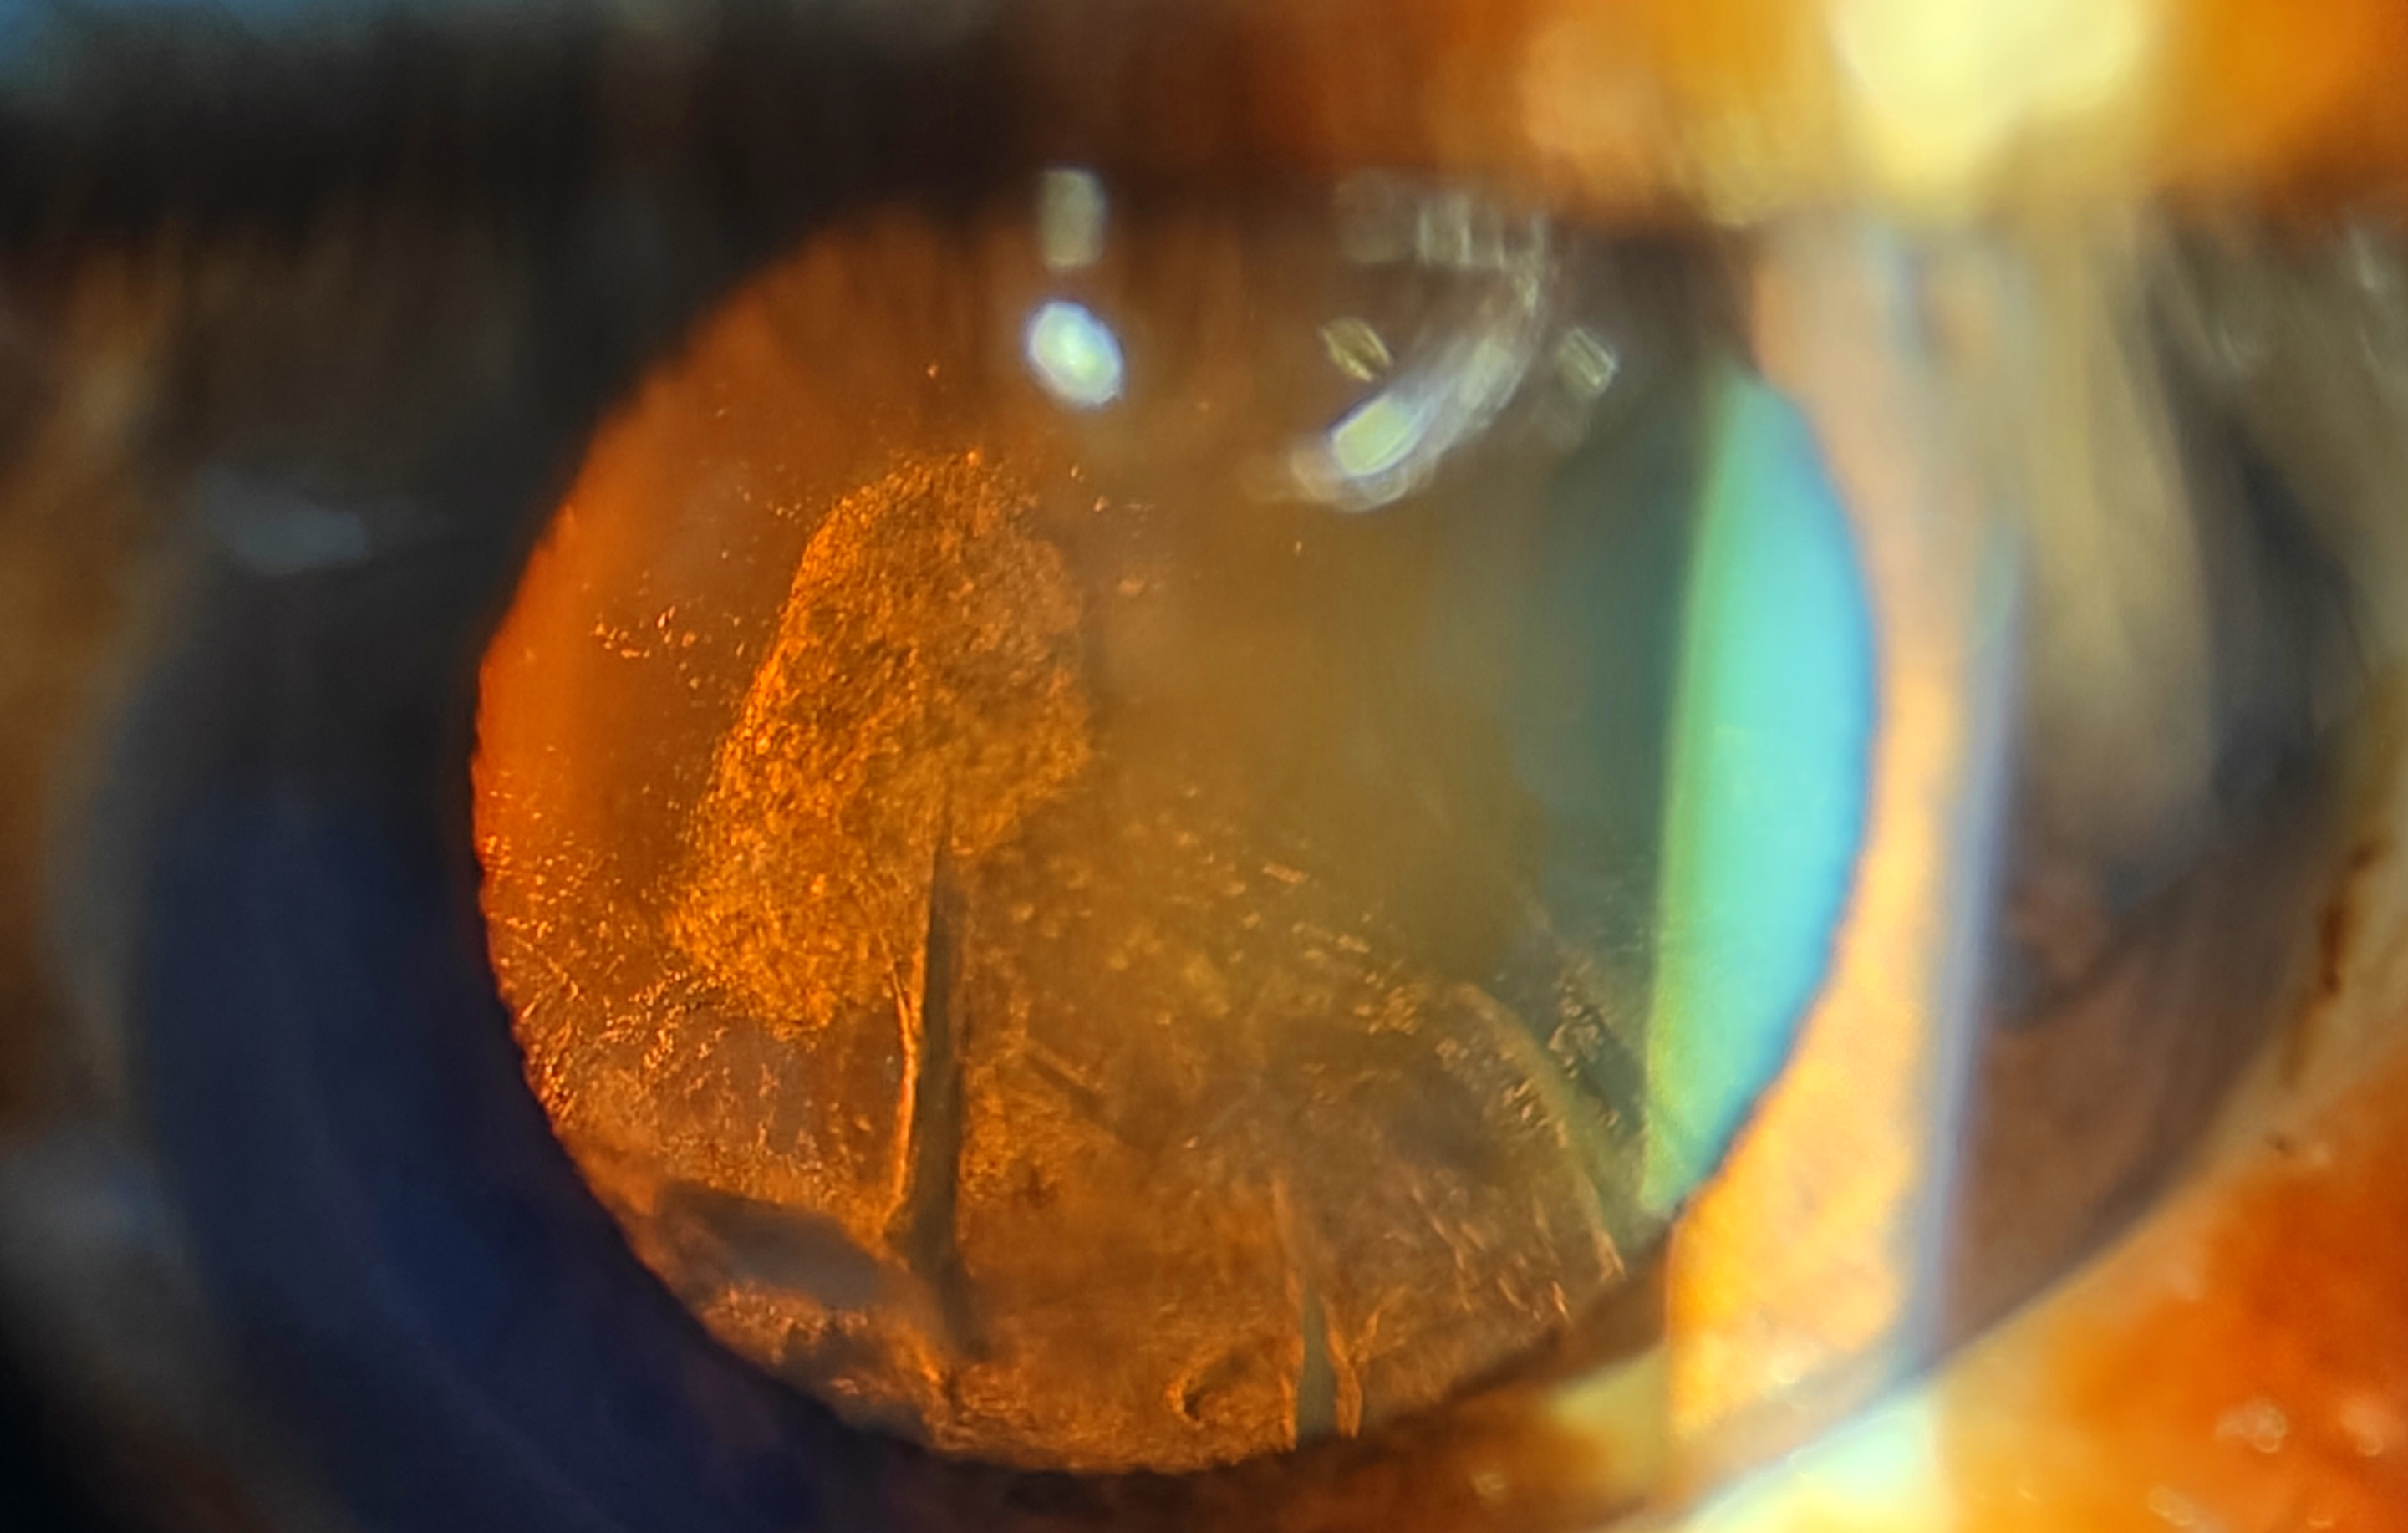

Freedom focus hydrophilic foldable IOLbecoming fully opaque after few years m

Author: Dr. Preethy Prasanth